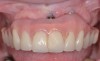

Fig 1. Patient presented with a screw-retained, full-arch restoration with full flange extension. Note there was no access for oral hygiene.

Figure 1

Fig 2. Upon removal of the prosthesis, plaque and debris were noted around the multi-unit abutments. Peri-implant mucositis was diagnosed.

Figure 2